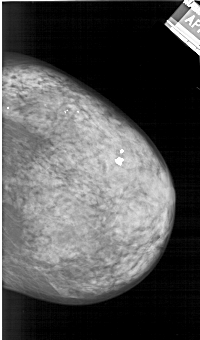

A_1242_1.LEFT_MLO

LEFT_CC LINES 6241 PIXELS_PER_LINE 3616 BITS_PER_PIXEL 12 RESOLUTION 43.5 OVERLAY

LEFT_MLO LINES 6541 PIXELS_PER_LINE 4051 BITS_PER_PIXEL 12 RESOLUTION 43.5 OVERLAY